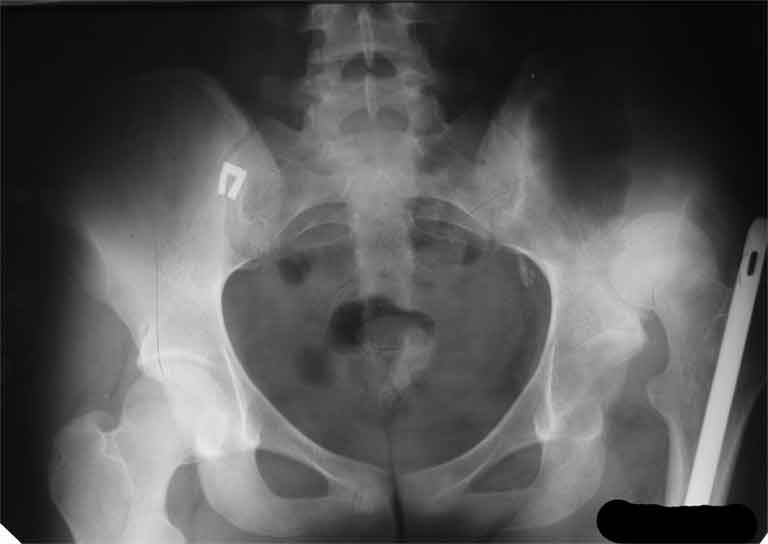

AV> опираясь на стул. На ногу не наступает. Укорочение 8 см. Иногда

А за счет чего такое укорочение? По снимку не видно соответствующего дефекта. Ну плюс приводящая контрактура - но все равно как-то уж больно много. Может, сделать снимки и таза обзорный с обоими проксимальными отделами бедра, и коенный суставов с приложенной линейкой какой?

The X ray that you provided does not show 8 cm of shortening. Perhaps you could send one showing the whole pelvis and proximal femurs.

I agree with Dr Eid's comments. The origin of the 8 cm leg length difference is a puzzle. Is this a clinical measurement? In that case contracture of the joint might affect the measurement. Can we see an AP pelvis to include both hip joints (including a calibration object with a known length) so that the difference in leg lengths that can be ascribed to the hip deformity and bony reabsorption can be measured. This sort of xray will help with templating for the TJR also. I would be very tempted to do a one stage procedure and accept some shortening. Shoe lifts should take care of a 3-4 cm difference.